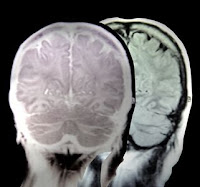

Vitamin B12 is one of the most important nutrients for your nerve cells- it plays an instrumental role in protecting and maintaining your nervous system impulses.Each nerve cell is protected by a fatty layer called myelin that insulates and allows for quick and efficient communication throughout the many other neurons of your brain and spinal cord.

Demyelinating diseases such as pernicious (megaloblastic) anemia and multiple sclerosis destroy the myelin of your nervous system, wearing it down to a thin layer, causing nervous reactions to slow down and malfunction.